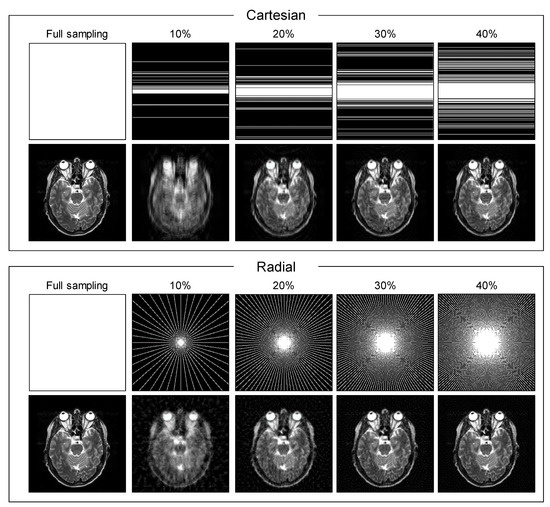

2. Materials and Methods

2.3. Experimental Setup